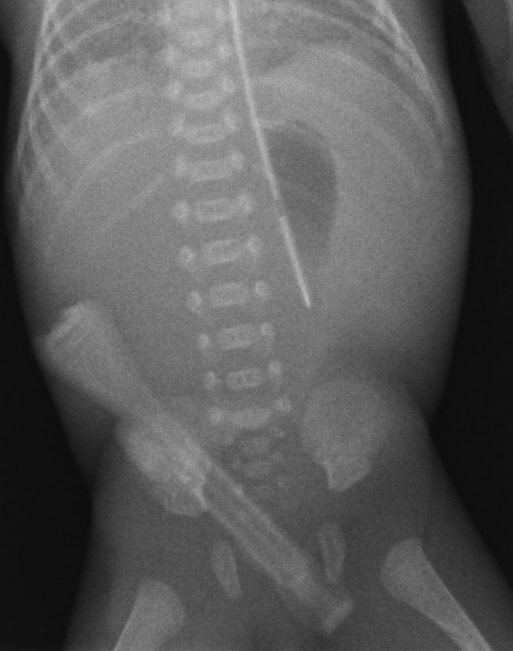

Original